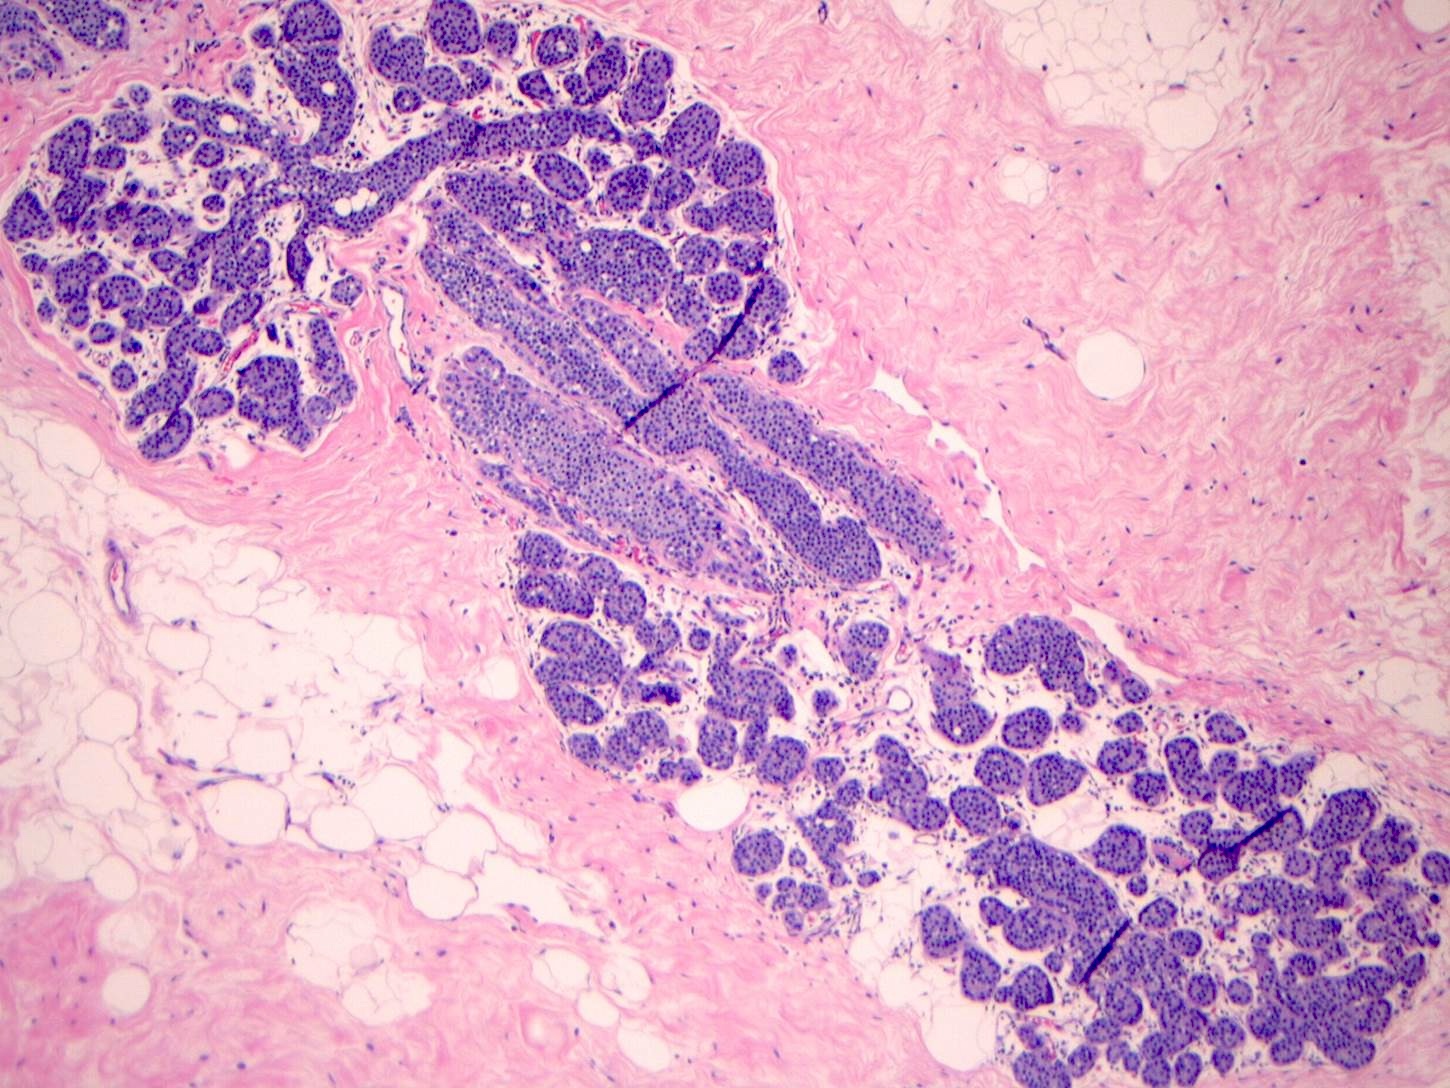

Microscopic (histologic) images

Contributed by Anna Biernacka, M.D., Ph.D.

Microscopic (histologic) description

- LCIS involves the terminal duct lobular unit (TDLU), filling and distending acini

- > 50% of the acini in a TDLU must be filled and expanded to qualify as LCIS; otherwise, called atypical lobular neoplasia

- Lobular distention is defined as the presence of ≥ 8 cells in the cross sectional diameter of an acinus

- LCIS most often involves lobules but may also grow along the basement membrane of ducts (i.e., pagetoid spread)

- Pagetoid spread in ducts is the characteristic growth of cells between luminal and myoepithelial layers of a duct without destroying ductal epithelium or filling up ductal lumina

- Often makes the ducts appear convoluted; this is called a cloverleaf pattern

- LCIS may secondarily involve (or arise in) sclerosing adenosis, radial scar, fibroadenoma, collagenous spherulosis or papilloma